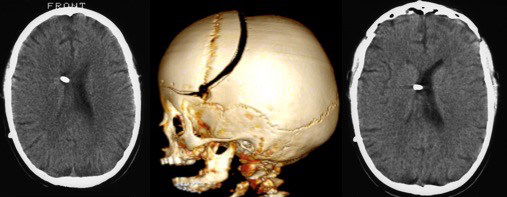

l’imagerie

elle élimine un processus tumoral et une hydrocéphalie ; elle montre la dilatation de la gaine arachnoïdienne du nerf optique, un aplatissement du globe, un soulèvement de la papille du nerf, une arachnoïdocèle intra-sellaire, une déformation du tronc cérébral.

elle étudie le drainage veineux qui peut être très anormal avec sténose ou atrophie des sinus avec circulation collatérale (ci-dessus), et hernie de villosités dans les sinus (ci contre).